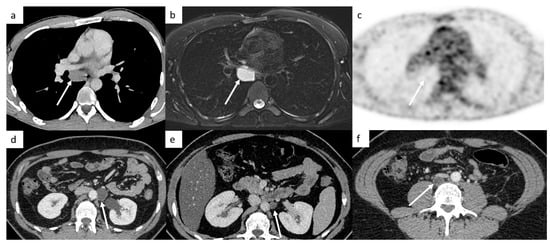

Mediastinal and hilar lymph nodes are not always metastatic disease and can correspond to granulomatous disease such as sarcoidosis or tuberculosis. Thorax CT can provide clues to distinguish them via the analysis of the pulmonary parenchyma. Other differential diagnoses are possible such as bronchogenic cysts (Figure 7).

Figure 7.

False-positive diagnoses. Thoracic CT shows a low-density mass below the carina in the middle mediastinum (a). A metastatic lymph node was suspected; however, this patient did not have any retroperitoneal lymph nodes. An MRI shows a well-circumscribed mass below the carina that appears hyperintense on T1-weighted images, hyperintense on T2-weighted images (b), without hypersignal on diffusion-weighted images. The FDG-PET CT confirms the absence of increased activity in this mass (c). It is a bronchogenic cyst. Post-surgical abdominal CT demonstrates a left paraaortic lymphocele (d) decreasing in size 3 months later, (e) but two years later, a low-density retrocaval mass appeared corresponding to teratoma (f). It shows that it can be difficult to differentiate teratoma from lymphocele, especially without prior CT to assess evolutions.

4.4.2. Retroperitoneal Lymph Node or Lymphocele?

Lymphocele is a cyst filled by lymph fluid that can occur after retroperitoneal lymphadenectomy. Most of the time, lymphoceles decrease in size over months after surgery and can resolve completely within a few months.

4.4.3. Teratoma versus Lymphocele

These entities can present similar features in CT examination. Lymphocele is present after surgery and will decrease in size with a cystic component most of the time (Figure 7), but it can have inflammatory reactions with a greater volume and a thicker wall. However, teratomas are not present on the immediate post-operative CT in cases of complete resection, appear during follow-up examinations and tend to increase in size. They are also cystic, but most of the time, there is tissular component. Sometimes, it is very difficult to differentiate lymphocele from teratoma, especially without prior CT to assess evolutions. MRI and contrast injection US can help to discriminate these two entities.